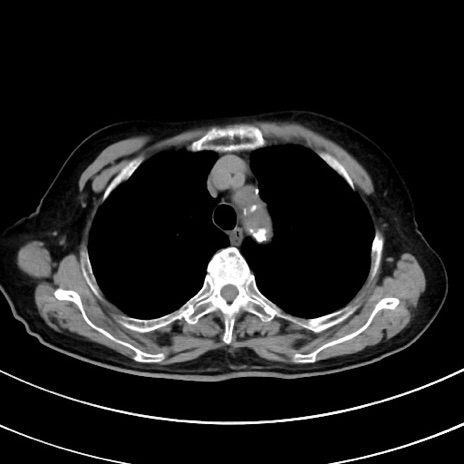

症例33(横断像)

【症例】70歳代 女性

【主訴】心窩部痛

【現病歴】延髄病変の精査・加療にて神経内科入院中。本日より心窩部痛あり。

【既往歴】虫垂炎

【身体所見】右下腹部を中心に圧痛と反跳痛あり。

【データ】WBC 10900、CRP 0.02